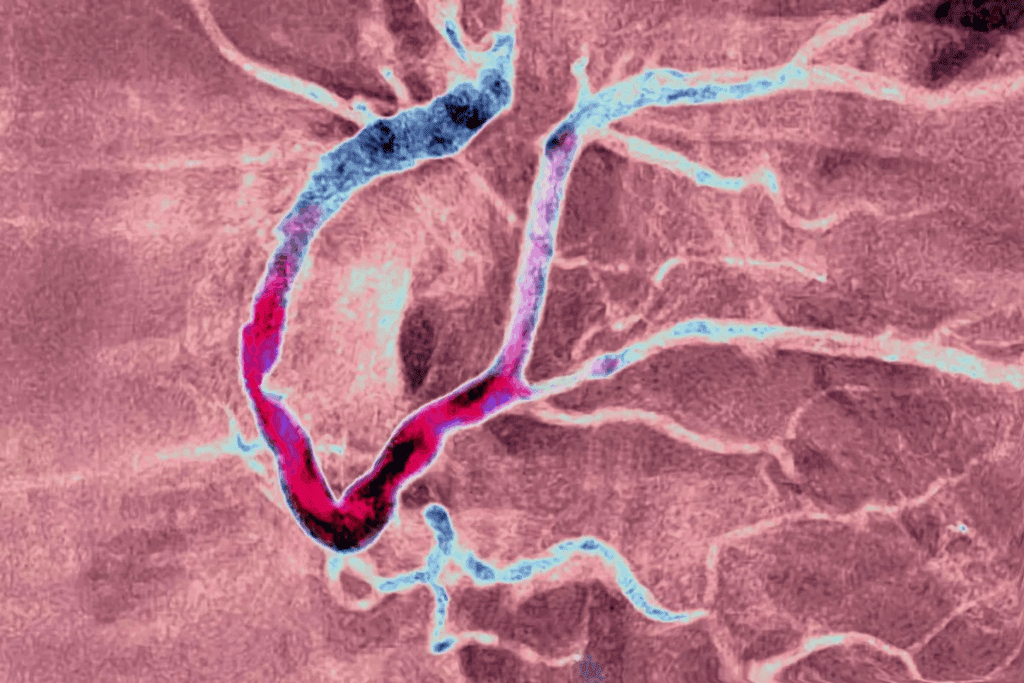

The Pathophysiology of Acute Coronary Syndrome

It’s important to know how acute coronary syndrome works to help patients quickly. ACS happens when the heart muscle doesn’t get enough blood. This usually happens because of a blockage in the coronary arteries.

Atherosclerosis and Plaque Rupture

Atherosclerosis plays a big role in ACS. It’s when fatty deposits, or plaques, build up in the heart’s arteries. If a plaque bursts, it can cause a blood clot. This clot might block blood flow to the heart.

Atherosclerosis gets worse over time. It can be caused by high blood pressure, high cholesterol, and smoking.

Coronary Thrombosis Formation

When a plaque bursts, it exposes blood to a very sticky material. This can start a blood clot in the coronary artery. This clot can block the artery, causing myocardial ischemia or infarction.

The clotting process is complex. It involves platelets getting active, sticking together, and starting the coagulation cascade.

Myocardial Ischemia and Infarction Process

Myocardial ischemia happens when the heart doesn’t get enough blood. This means it can’t get enough oxygen. If this goes on for too long, it can cause a heart attack.

Understanding how ACS works is key to treating it right. Knowing the pathophysiology helps doctors give the best care. This can lead to better outcomes for patients.